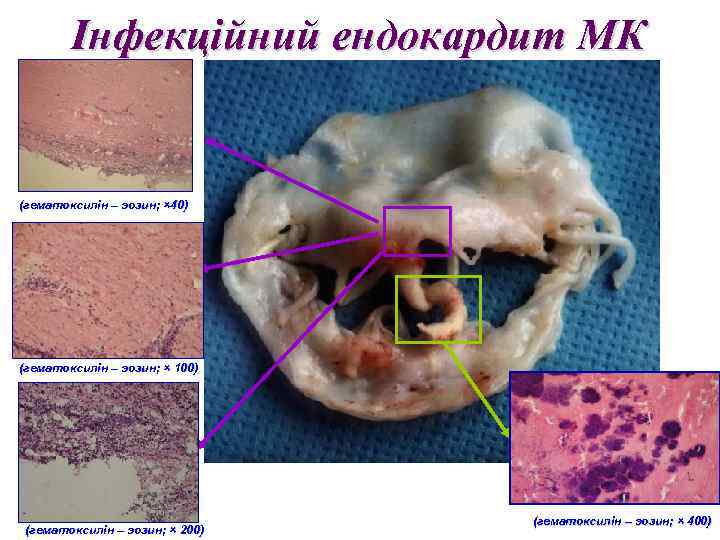

Інфекційний ендокардит МК (гематоксилін – эозин; × 40) (гематоксилін – эозин; × 100) (гематоксилін – эозин; × 200) (гематоксилін – эозин; × 400)